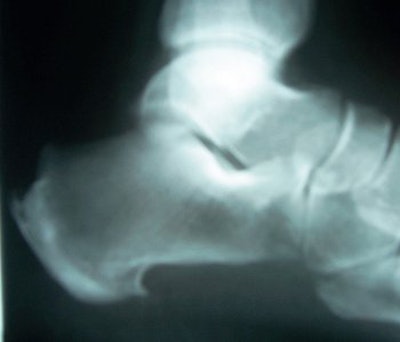

| If the frontal sinuses (above) of an unidentified corpse are intact, they can be as distinctive as fingerprints. Bone spurs (below) can also be unique identifying markers, as these two example x-rays show. Images courtesy of Nancy Adams. |

Adams offered some details on how forensics experts apply imaging to body identification. Frontal sinuses "can be as unique as fingerprints," she said. "You also do the feet. There will be bone spurs on the heels. Another thing is the legs. One individual had a total knee replacement."